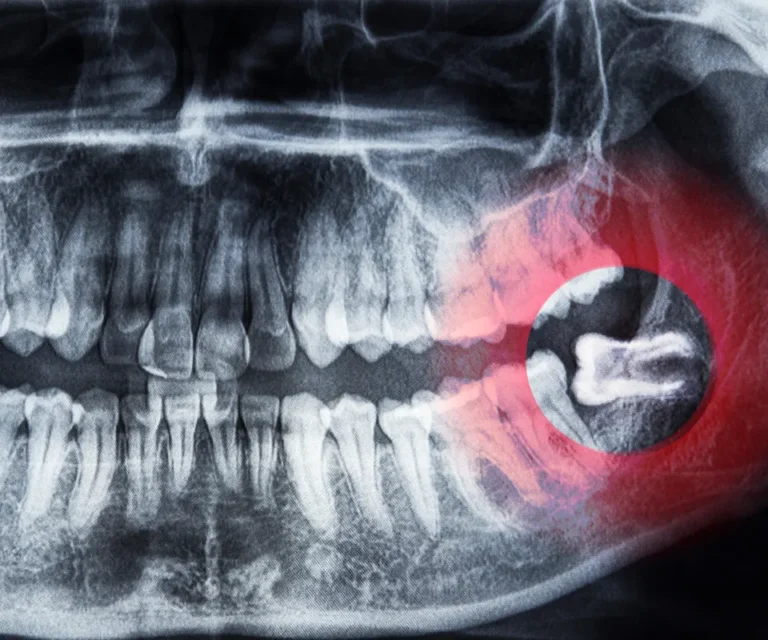

Wisdom Tooth Infection Emergencies

Wisdom teeth are especially prone to infection due to their position in the back of your mouth, making them harder to clean. Common signs of a wisdom tooth infection include:

Our emergency dentists in Covington can assess whether you need antibiotics, drainage, or immediate extraction to eliminate infection and pain.